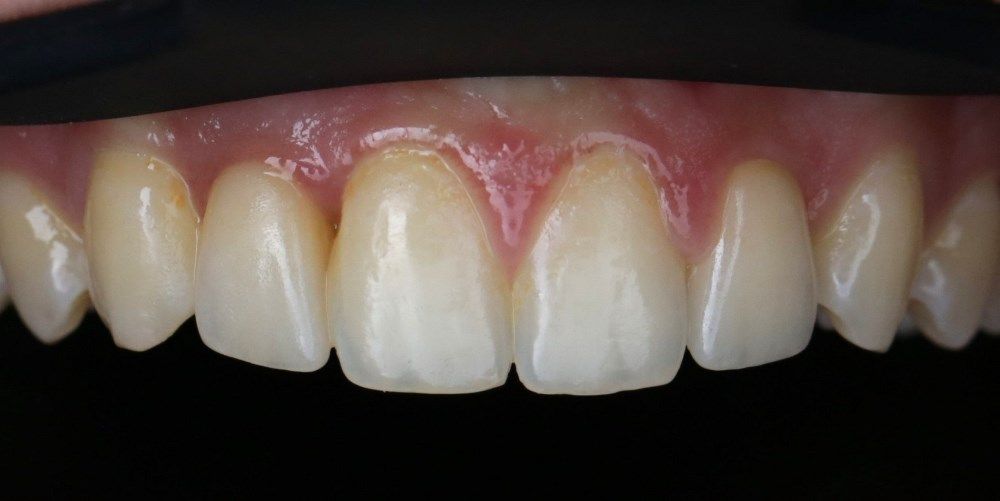

фото коронок

после

до